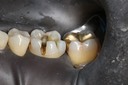

Gary Umeda #18,19,20 pre-op

Gary Umeda #18, 19, 20 prep